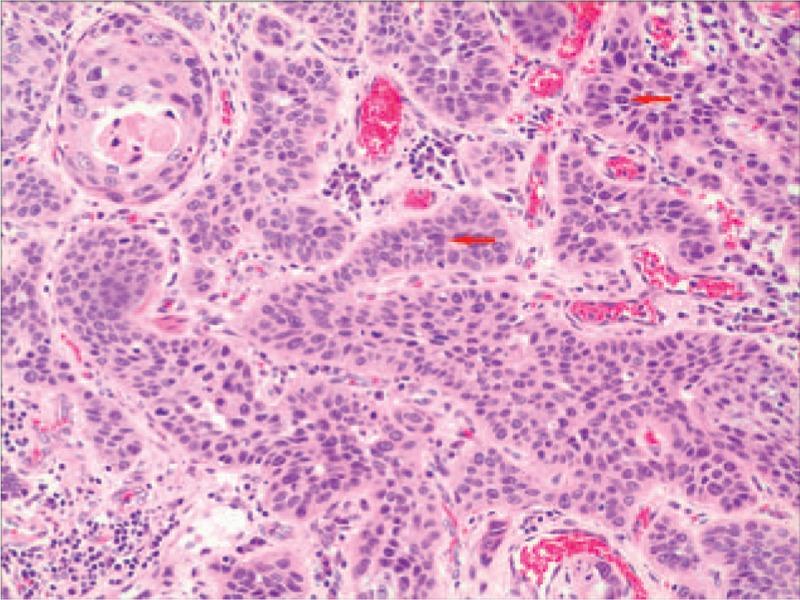

We performed esophagectomy, esophagogastrostomy through the esophageal bed and 2-field lymphadenectomy. Histopathological analysis of the tumor revealed histological characteristics typical of an esophageal MEC. Radio-chemotherapy was administered to this patient.

我们进行了食管切除术、经食管床食管胃吻合术和二野淋巴结清扫术。肿瘤的组织病理学分析显示出食管MEC典型的组织学特征。对该患者进行了放化疗。